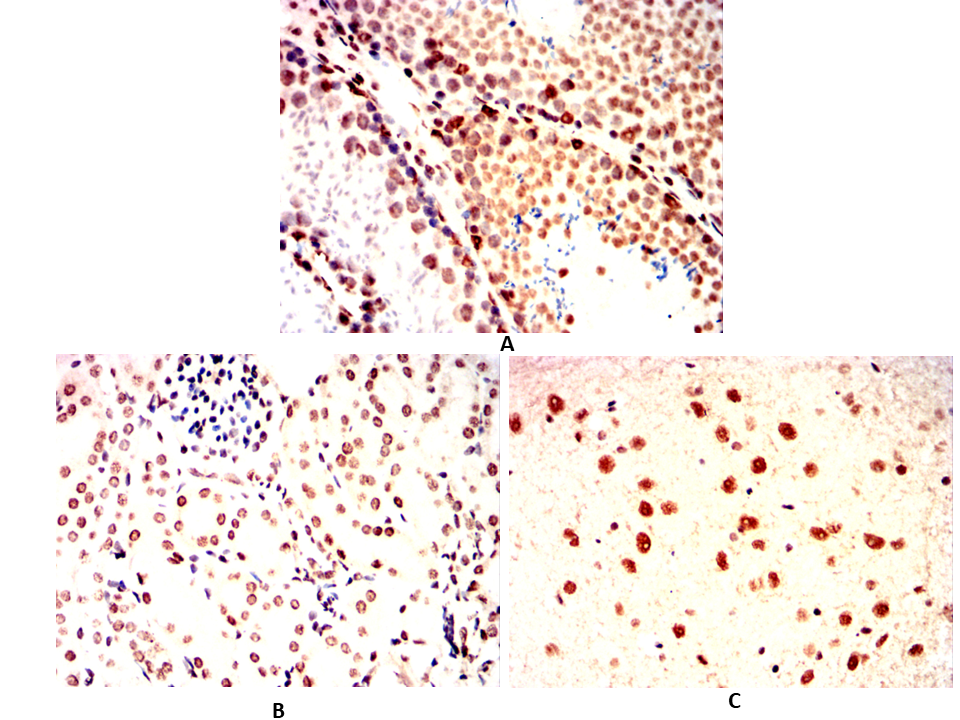

Immunohistochemical analysis of paraffin-embedded Rat testicles(A)Rat kidney(B)Rat cerebellum(C) using EBF1 mouse mAb with DAB staining.